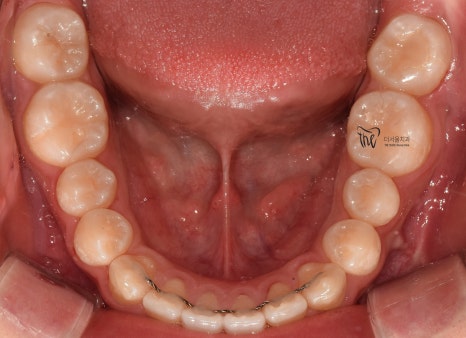

교합면에서 봤을 때는, 거의 무턱 교정 치료가

다 끝난거와 같은 느낌을 받으실 수 있습니다.

원래, 악궁 자체는 그렇게 나쁜 편은

아니였기 때문에 크게 달라졌다고 느낌을

받기는 쉽지 않네요.

처음에 오셨을 때, 총생의 정도가 심했다면

전후 가 조금 더 명확했을 듯 합니다.

『교정 치료 종료, 전후 공개』

이제, 아래턱이 조금 튀어나온 듯한 느낌을

받을 수 있습니다.